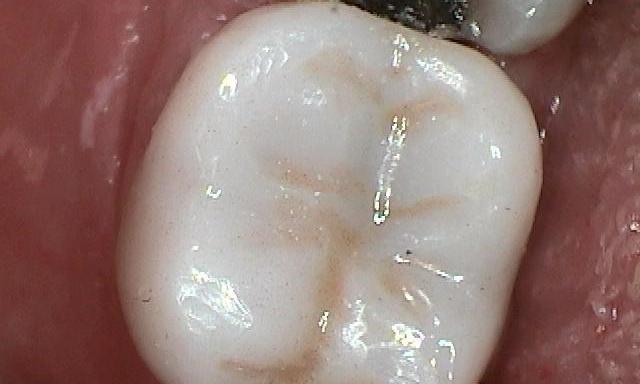

The tooth in the Before photo has a silver filling with quite a few cracks in the tooth. All back teeth have peaks (cusps) and valleys (grooves) allowing to chew your food. Cracks often occur in the valleys of these teeth and around the peaks. These cracks increase the potential for these peaks to break off over time. On this tooth we monitored the cracks and when they began increasing in size, we recommended a crown. A crown (sometimes referred to as a cap) surrounds the tooth 360 degrees. This prevents any part of the tooth or the peaks ...